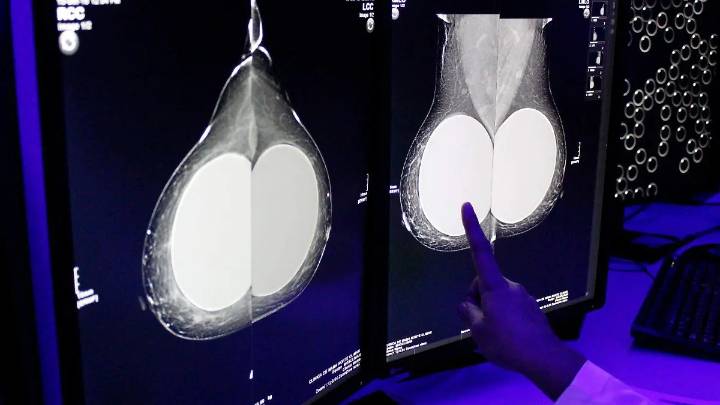

Se adquirirán mil mastógrafos y se crearán 20 centros de interpretación de estudios, así como un centro de atención oncológica para mujeres en cada entidad del país

Con motivo del Día Internacional de la Lucha contra el Cáncer de Mama, la presidenta Claudia Sheinbaum Pardo anunció la puesta en marcha del Modelo de Atención Universal de Cáncer de Mama, una estrategia nacional que busca fortalecer la detección temprana, diagnóstico y tratamiento oportuno de esta enfermedad en todo el país.

Durante su mensaje en video difundido en redes sociales, Sheinbaum recordó que en México muere una mujer cada hora a causa del cáncer de mama, cifra que podría reducirse significativamente con una atención oportuna.